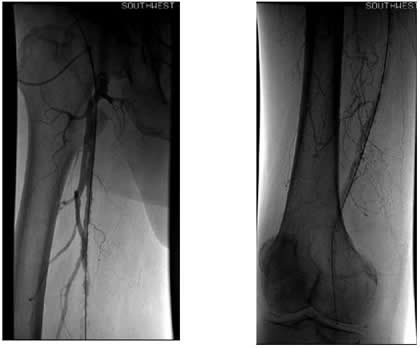

Case 4: A 67-year-old woman with diabetes and tissue loss in the foot secondary to pressure injury with poor healing. Angiogram through an antegrade approach shows a small vessel (average diameter 3 mm) with proximal occlusion and segmental stensoses (Figure 4A). After angioplasty followed by cryoablation, the proximal stenotic areas were treated with 5 mm diameter coronary self-expanding bare stents (Figure 4B). The foot has now healed.